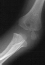

- XRAYS: Radiographic examination of the right upper extremity revealed

a displaced fracture involving the lateral condylar physis exiting through

the substance of the capitellum.